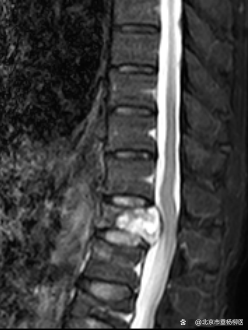

原来在一年前,黄老因罹患肾脏肿瘤行左肾切除术,但术后病理不详。脊柱外科(骨四科)主任姜树东在得知这一情况后,立即为患者完善胸腰椎核磁共振检查。结果提示T12椎体骨质破坏,结构不完整,向后压迫硬膜囊,椎管狭窄,脊髓受压;周围软组织肿胀;考虑病理性骨折(T12),脊柱转移瘤可能性大。随后,再行T12椎体穿刺活检术。同时患者家属提供了患者的既往病历:左肾肿瘤符合透明细胞癌。

▲术前检查

椎骨活检病理结果显示:(T12椎体内组织)送检少许破碎骨组织、多量纤维结缔组织及纤维素渗出坏死组织。纤维结缔组织部分间质疏松水肿,部分区域细胞密集,局灶可见透明细胞浸润。结合病史及免疫组化结果,符合肾透明细胞癌转移。